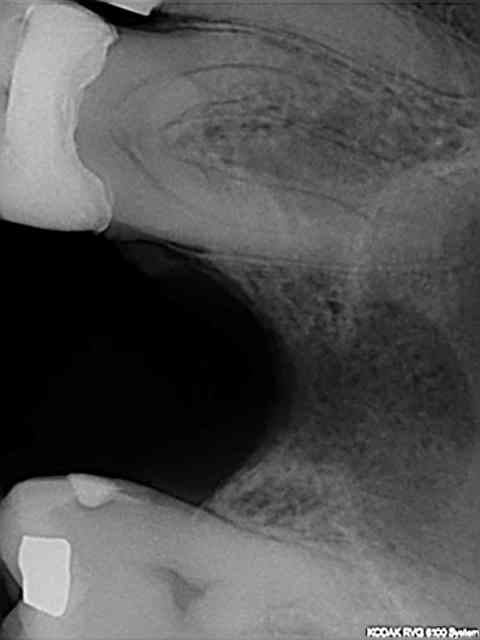

11-12: RX avant-après